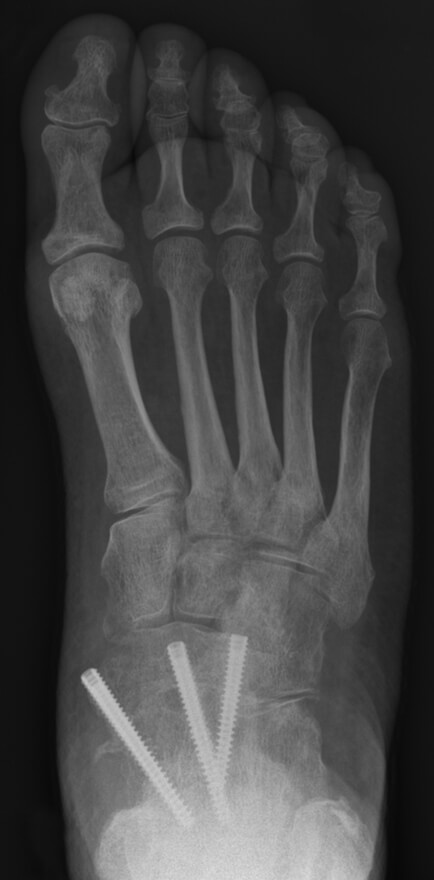

Tijdens de operatie wordt een snee in de huid gemaakt aan de buitenzijde van de enkel. Het beschadigde kraakbeen van het gewricht wordt volledig verwijderd. Vervolgens worden de botten stevig aan elkaar bevestigd met één of meerdere schroeven. In gevallen waarin veel bot is aangetast door de artrose, kan soms een bottransplantatie nodig zijn. Hierbij zal de specialist waarschijnlijk een stukje van uw eigen bot gebruiken, meestal uit uw onderbeen, hielbeen of bekken.

Op de röntgenfoto's ziet u dat het sprongbeen met drie schoeven aan de talus is vastgezet.